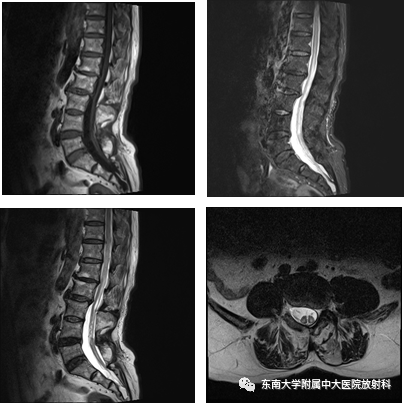

脊髓拴系综合征

主诉:排尿困难半年,双下肢麻木、乏力2月余

现病史:患者半年前出现排尿困难,进行性加重,偶尔伴有尿道酸胀、疼痛,2月余前出现脐以下双下肢麻木,并伴有双下肢乏力

查体:双下肢浅感觉减退,深感觉正常